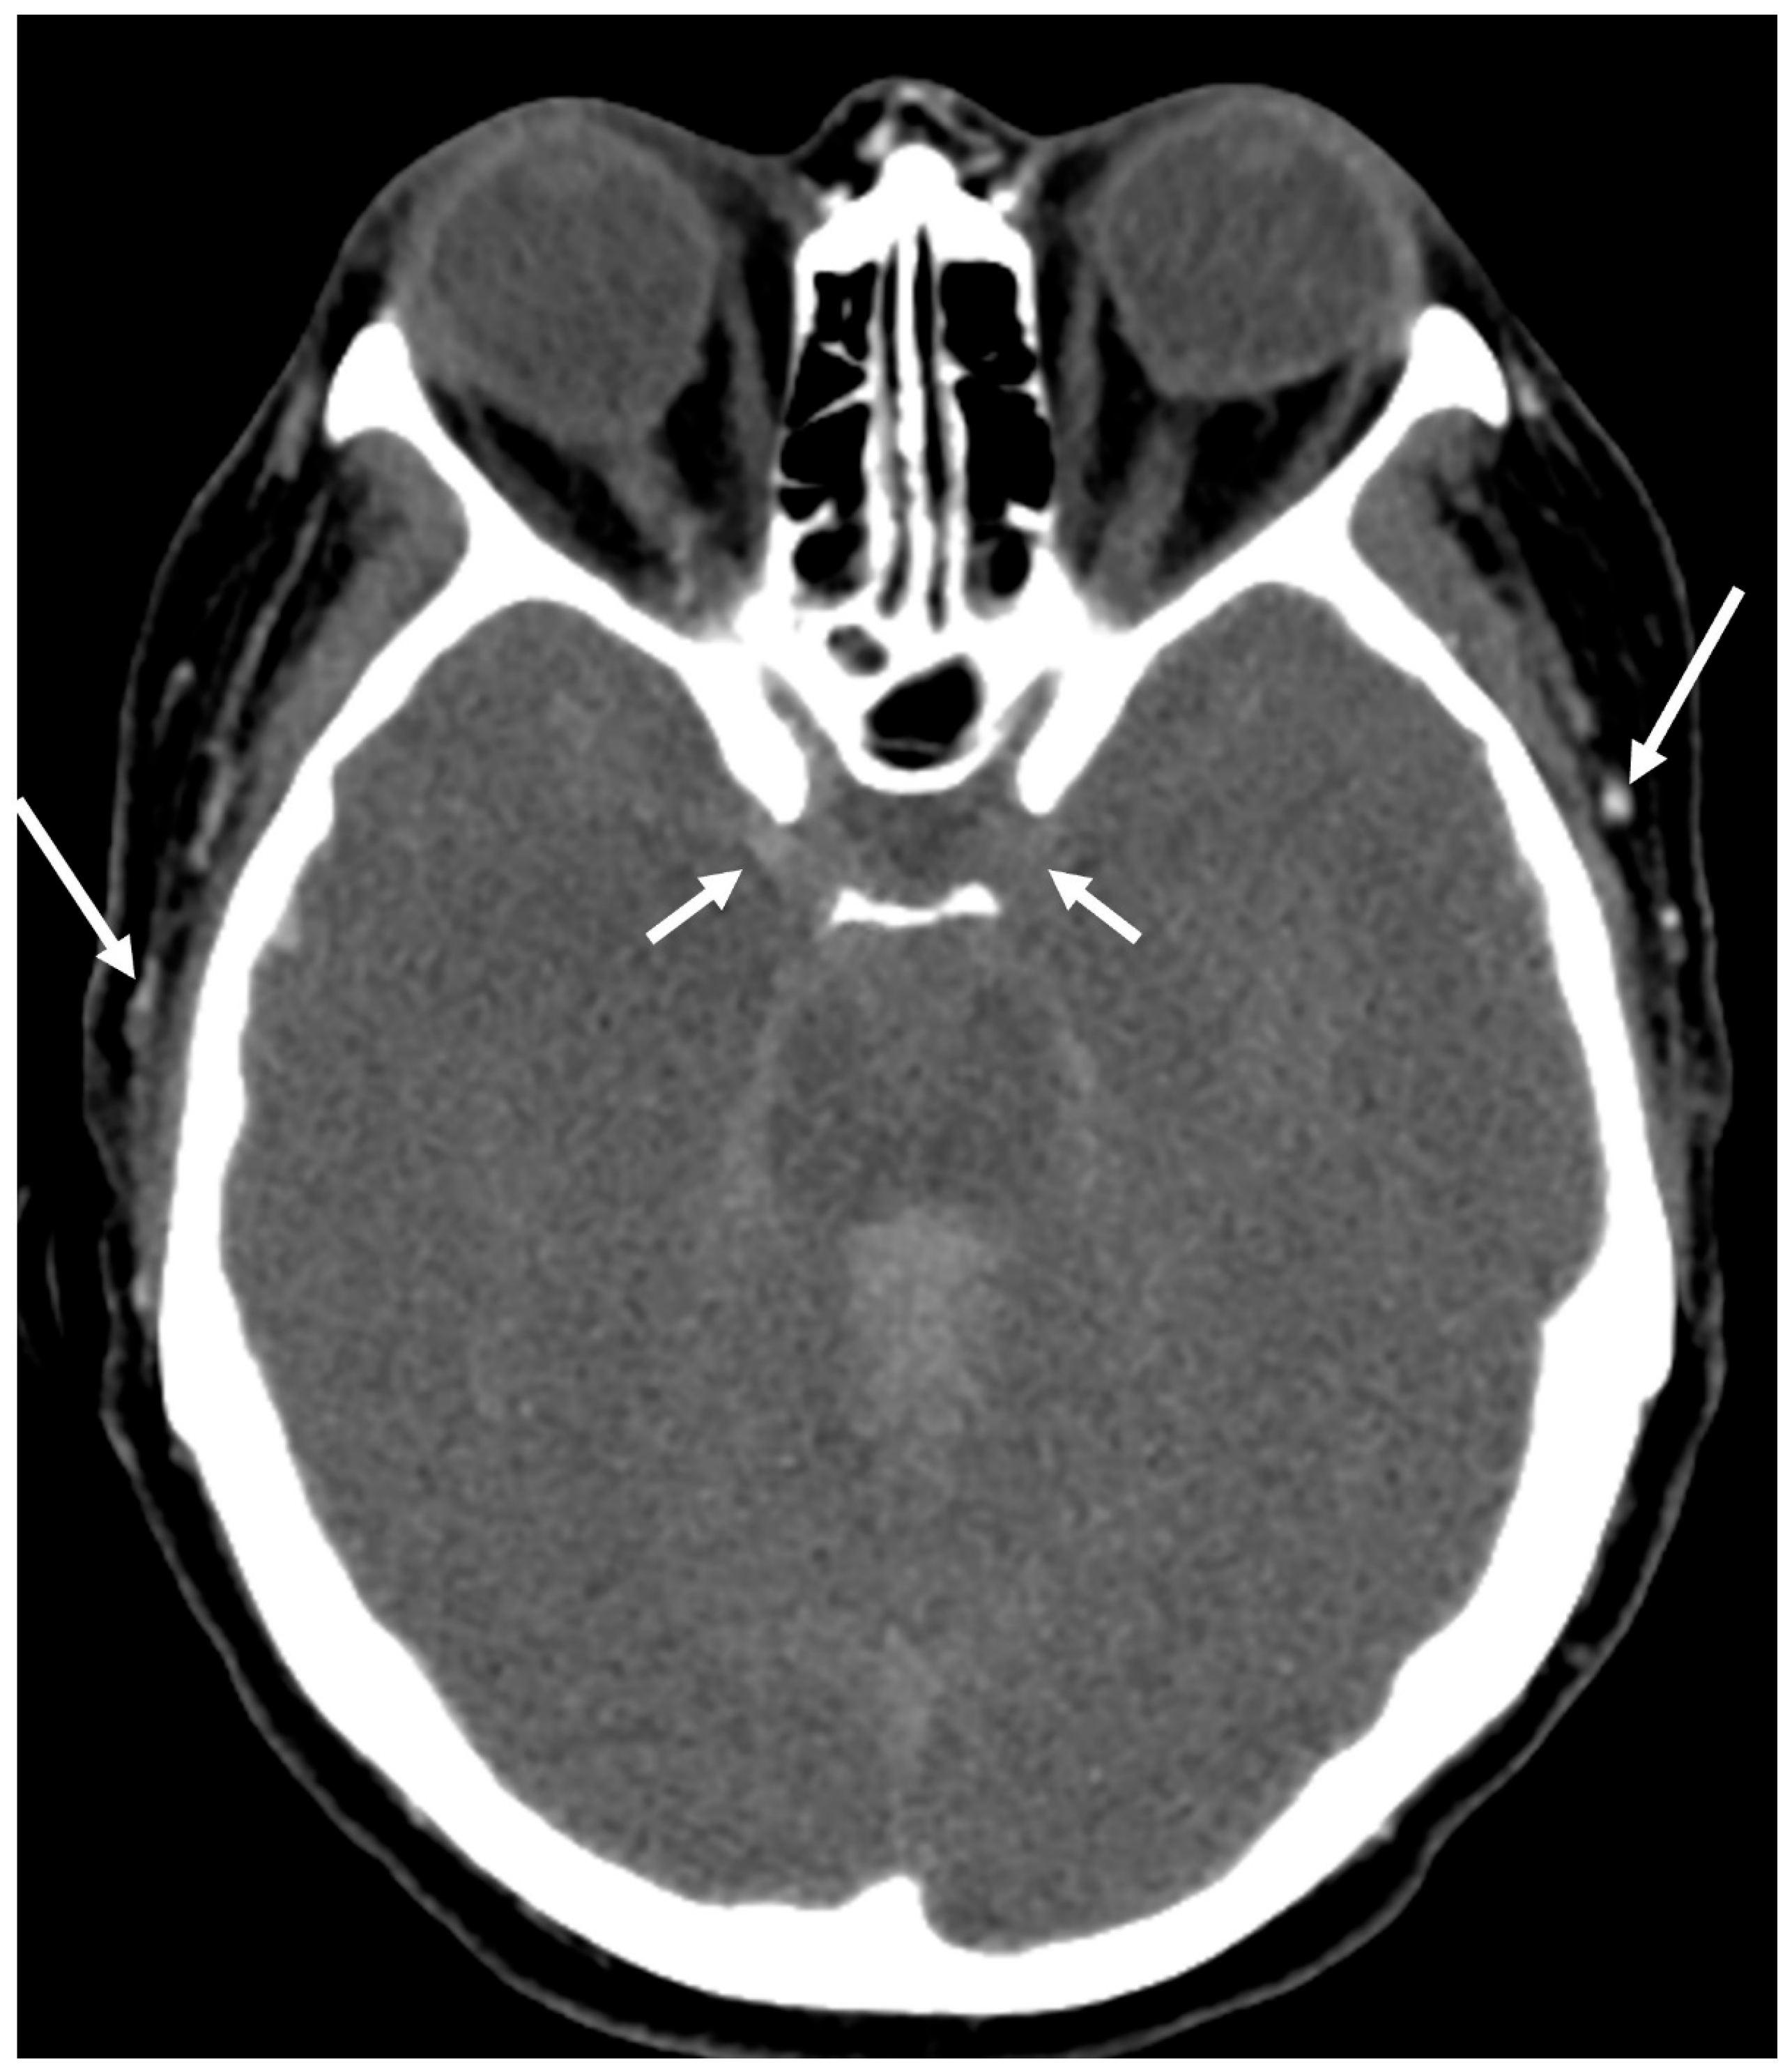

Figure 3. CTA showing opacification of intracranial arteries but no opacification of the deep venous system (a,b). On the same day, a digital subtraction angiogram of the right (c) and left (d) common carotid arteries and dominant right vertebral artery (e) showed no filling of intracranial arteries but continued filling of the extracranial arteries, consistent with findings of DNC. This is based on most of the scoring system criteria, but DNC cannot be confirmed except using the venous score.

• The venous score assigns one point each for non-opacification of both the ICVs and the superior petrosal veins (Figure 3).

While most scoring systems prioritize the evaluation of both arterial and venous systems, venous scoring systems focus exclusively on assessing the filling of the deep venous system. The principle underlying this approach is that if the brain maintains sufficient blood flow for viability, contrast flow from the arterial to the venous side should be detectable. Although the superficial venous system could potentially fill from the extracranial circulation, the deep venous system relies solely on intracranial circulation for adequate filling. Any opacification of the venous system precludes a diagnosis of DNC (Figure 3). Hence, an adequate venous phase is critical for the diagnosis of brain death. This raises questions about the necessity of arterial opacification in any of the scoring systems. While no scoring system has proven superior to others, it is intuitive that the more vessels included in the scoring system, the lower its sensitivity will be in diagnosing DNC. This is crucial because the purpose of an ancillary test is not only to diagnose DNC but also to rule out its absence. A scoring system that includes a larger number of blood vessels is more reliable regarding falsely declaring someone brain dead, whereas a scoring system that includes fewer blood vessels is simpler and likely more accurate in confirming DNC.